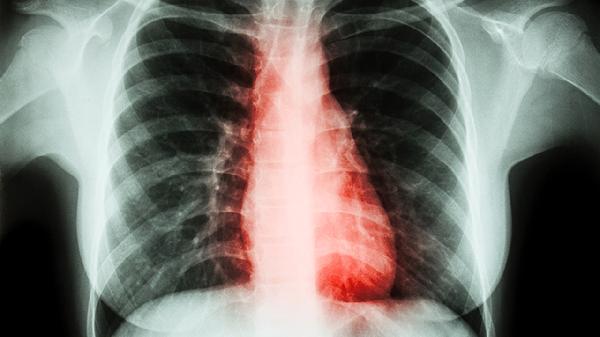

肺部二氧化碳过高怎么治疗

肺部二氧化碳过高可通过氧疗、药物治疗、机械通气、调整生活方式、治疗原发病等方式改善。肺部二氧化碳过高可能与慢性阻塞性肺疾病、呼吸肌无力、中枢性呼吸抑制、严重肺炎、胸廓畸形等因素有关。